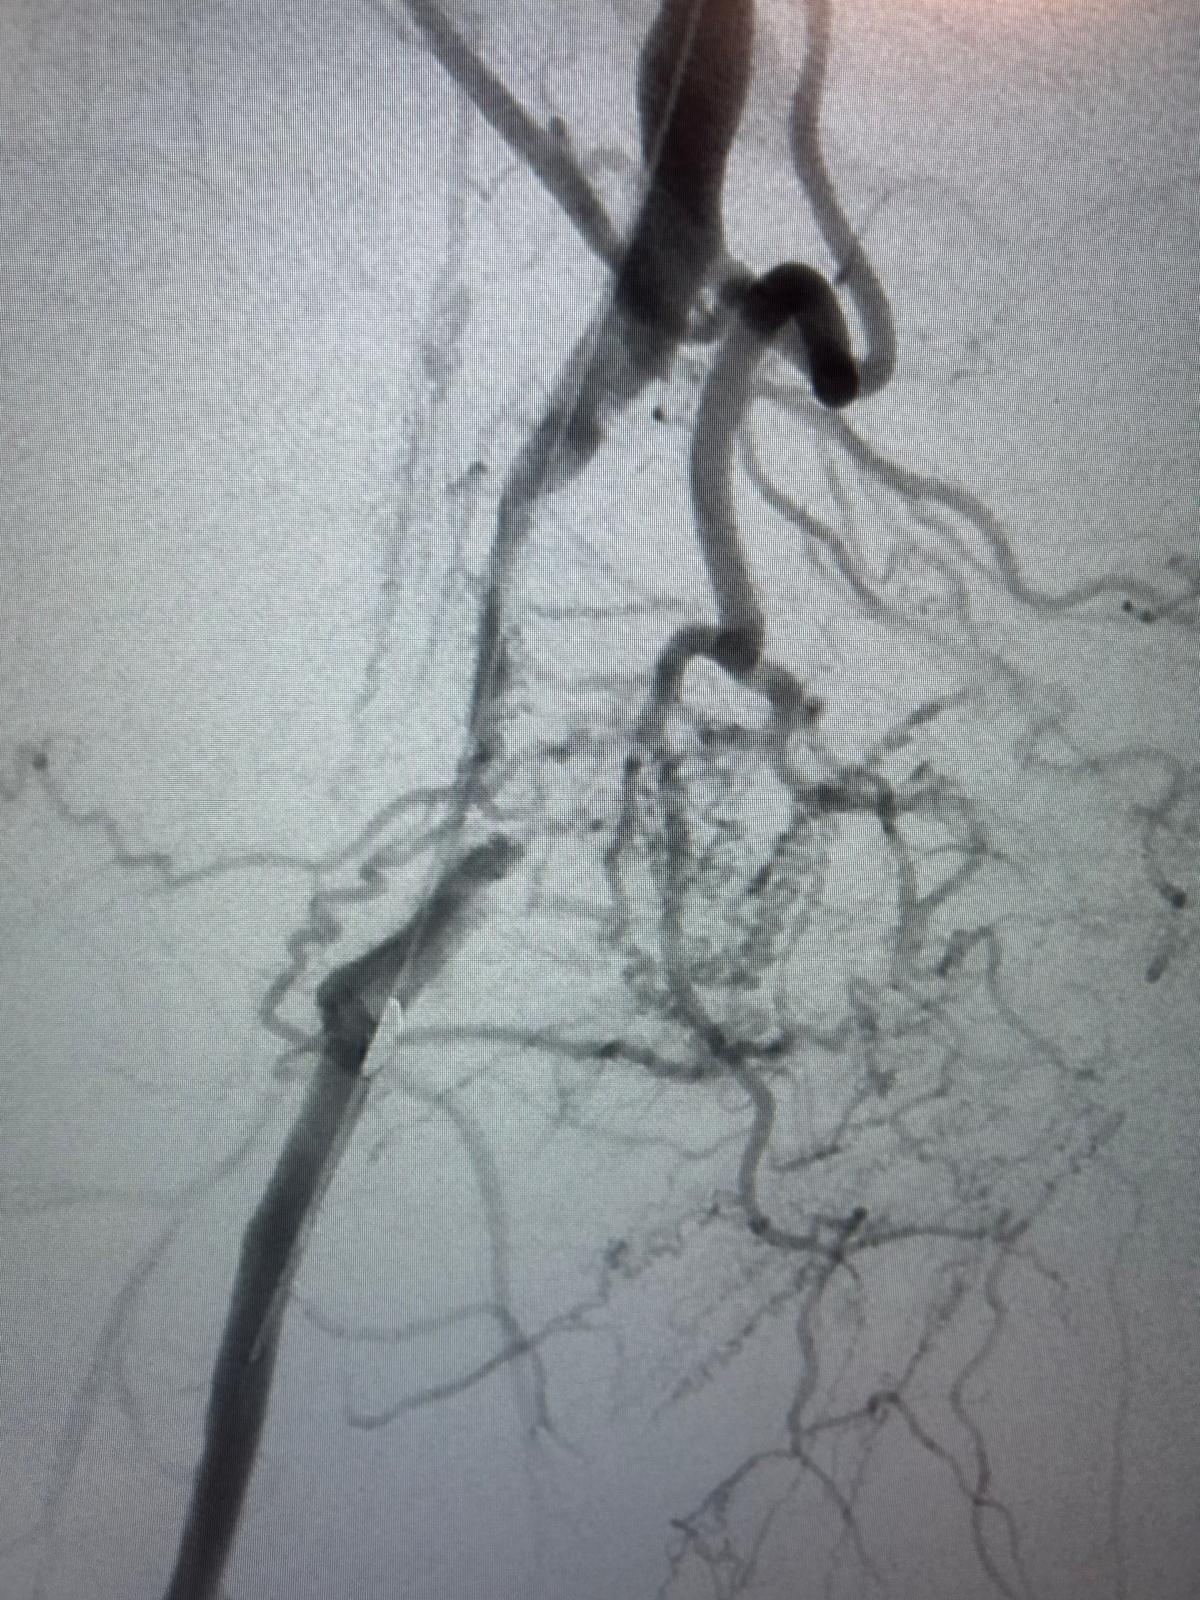

Résultat

Excellent résultat anatomique immédiat au contrôle artériographique per-opératoire.

Respect de la perméabilité de l'ostium de l'artère fémorale profonde et de ses collatérales au niveau de la jonction fémoro-poplitée.

Aucune embolisation distale per-opératoire constatée au niveau des artères de jambe et du pied.

Très bonne revascularisation clinique du pied et excellent pouls tibial postérieur droit.